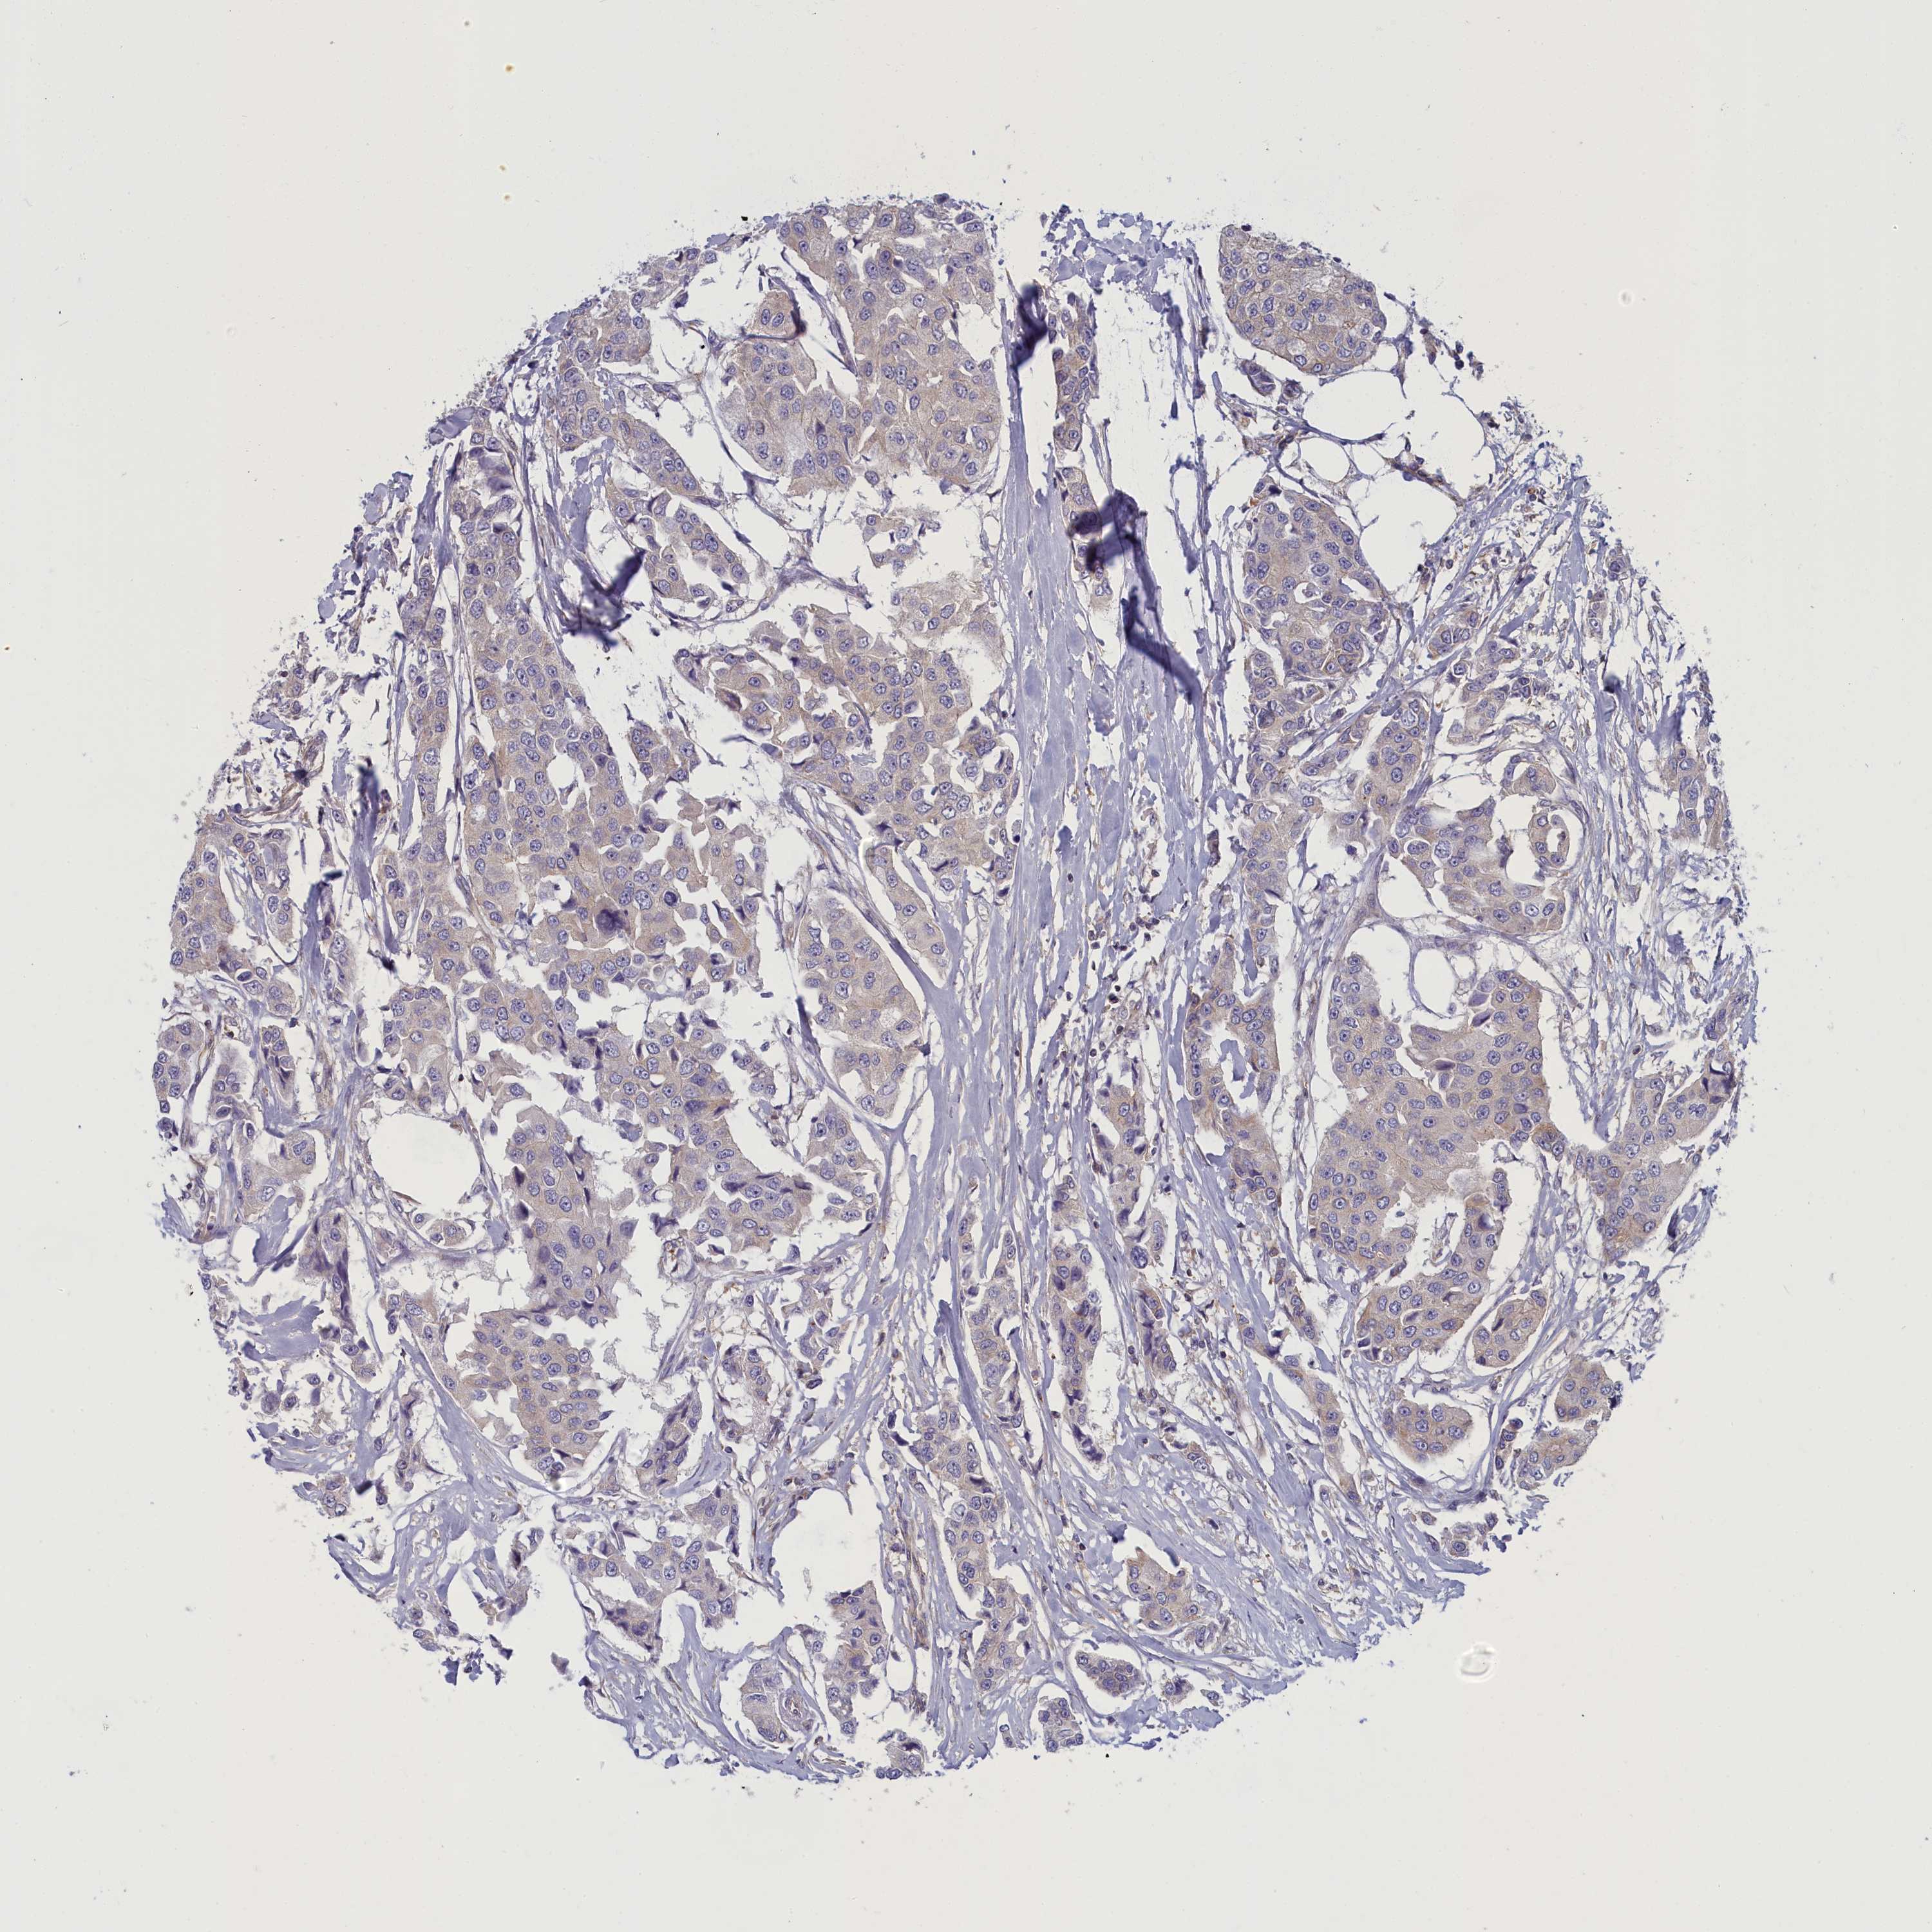

CANCER BREAST CANCER Show tissue menu

BRCA TCGA BRCA VALIDATION PROTEIN EXPRESSION

ANTIBODIES

AND

VALIDATION